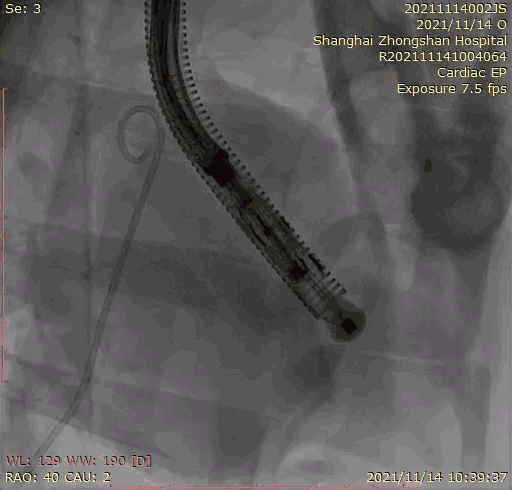

本次臨床前研究經(jīng)右側(cè)頸靜脈置入LuX-Valve Plus輸送系統(tǒng)可調(diào)彎鞘管,在DSA及超聲引導下將人工三尖瓣瓣膜植入到原有三尖瓣位置,利用獨特的錨定技術(shù)將人工瓣膜支架可靠固定在預(yù)定的位置。

上海中山醫(yī)院葛均波院士、錢菊英院長、周達新教授、潘文志教授、潘翠珍教授、李偉教授共同完成此次臨床前研究。術(shù)后葛均波院士對Lux-Valve Plus的器械操作性能給予了高度評價,DSA和超聲影像也顯示出在本次研究中Lux-Valve Plus的安全性和有效性俱佳。